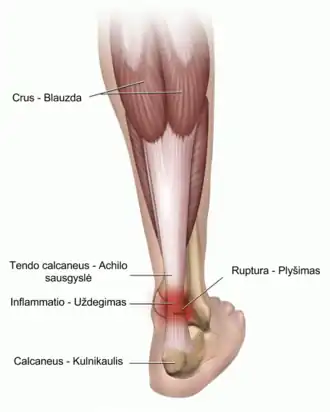

Le tendon est la partie du muscle en forme de cordons qui prolonge le corps musculaire.

Les tendons sont plus résistants que les ligaments mais la répétition d'activités comme l'entraînement chez le sportif de haut niveau ou les stimulations répétées propres à certains métiers ou activités manuelles peuvent induire diverses lésions comme des tendinites (inflammations de certains tendons) et une fragilisation du tendon qui peut se déchirer ou se rompre. Certaines maladies (maladie de Lyme) peuvent aussi se traduire par des arthrites avec affection douloureuse des tendons.

Ces lésions du tendon s'appellent des tendinopathies ou tendinoses (lésions sans inflammation).

- Tendon d'Achille